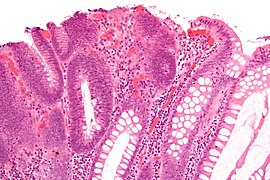

Tubulovillous adenoma 20% to 25%[18] 25%-75% villous[17] Micrograph of tubulovillous adenoma.jpg

Villous adenoma 15%[19] to 40%[18] Over 75% villous[17] Villous adenoma of the colorectum (high power view).jpg